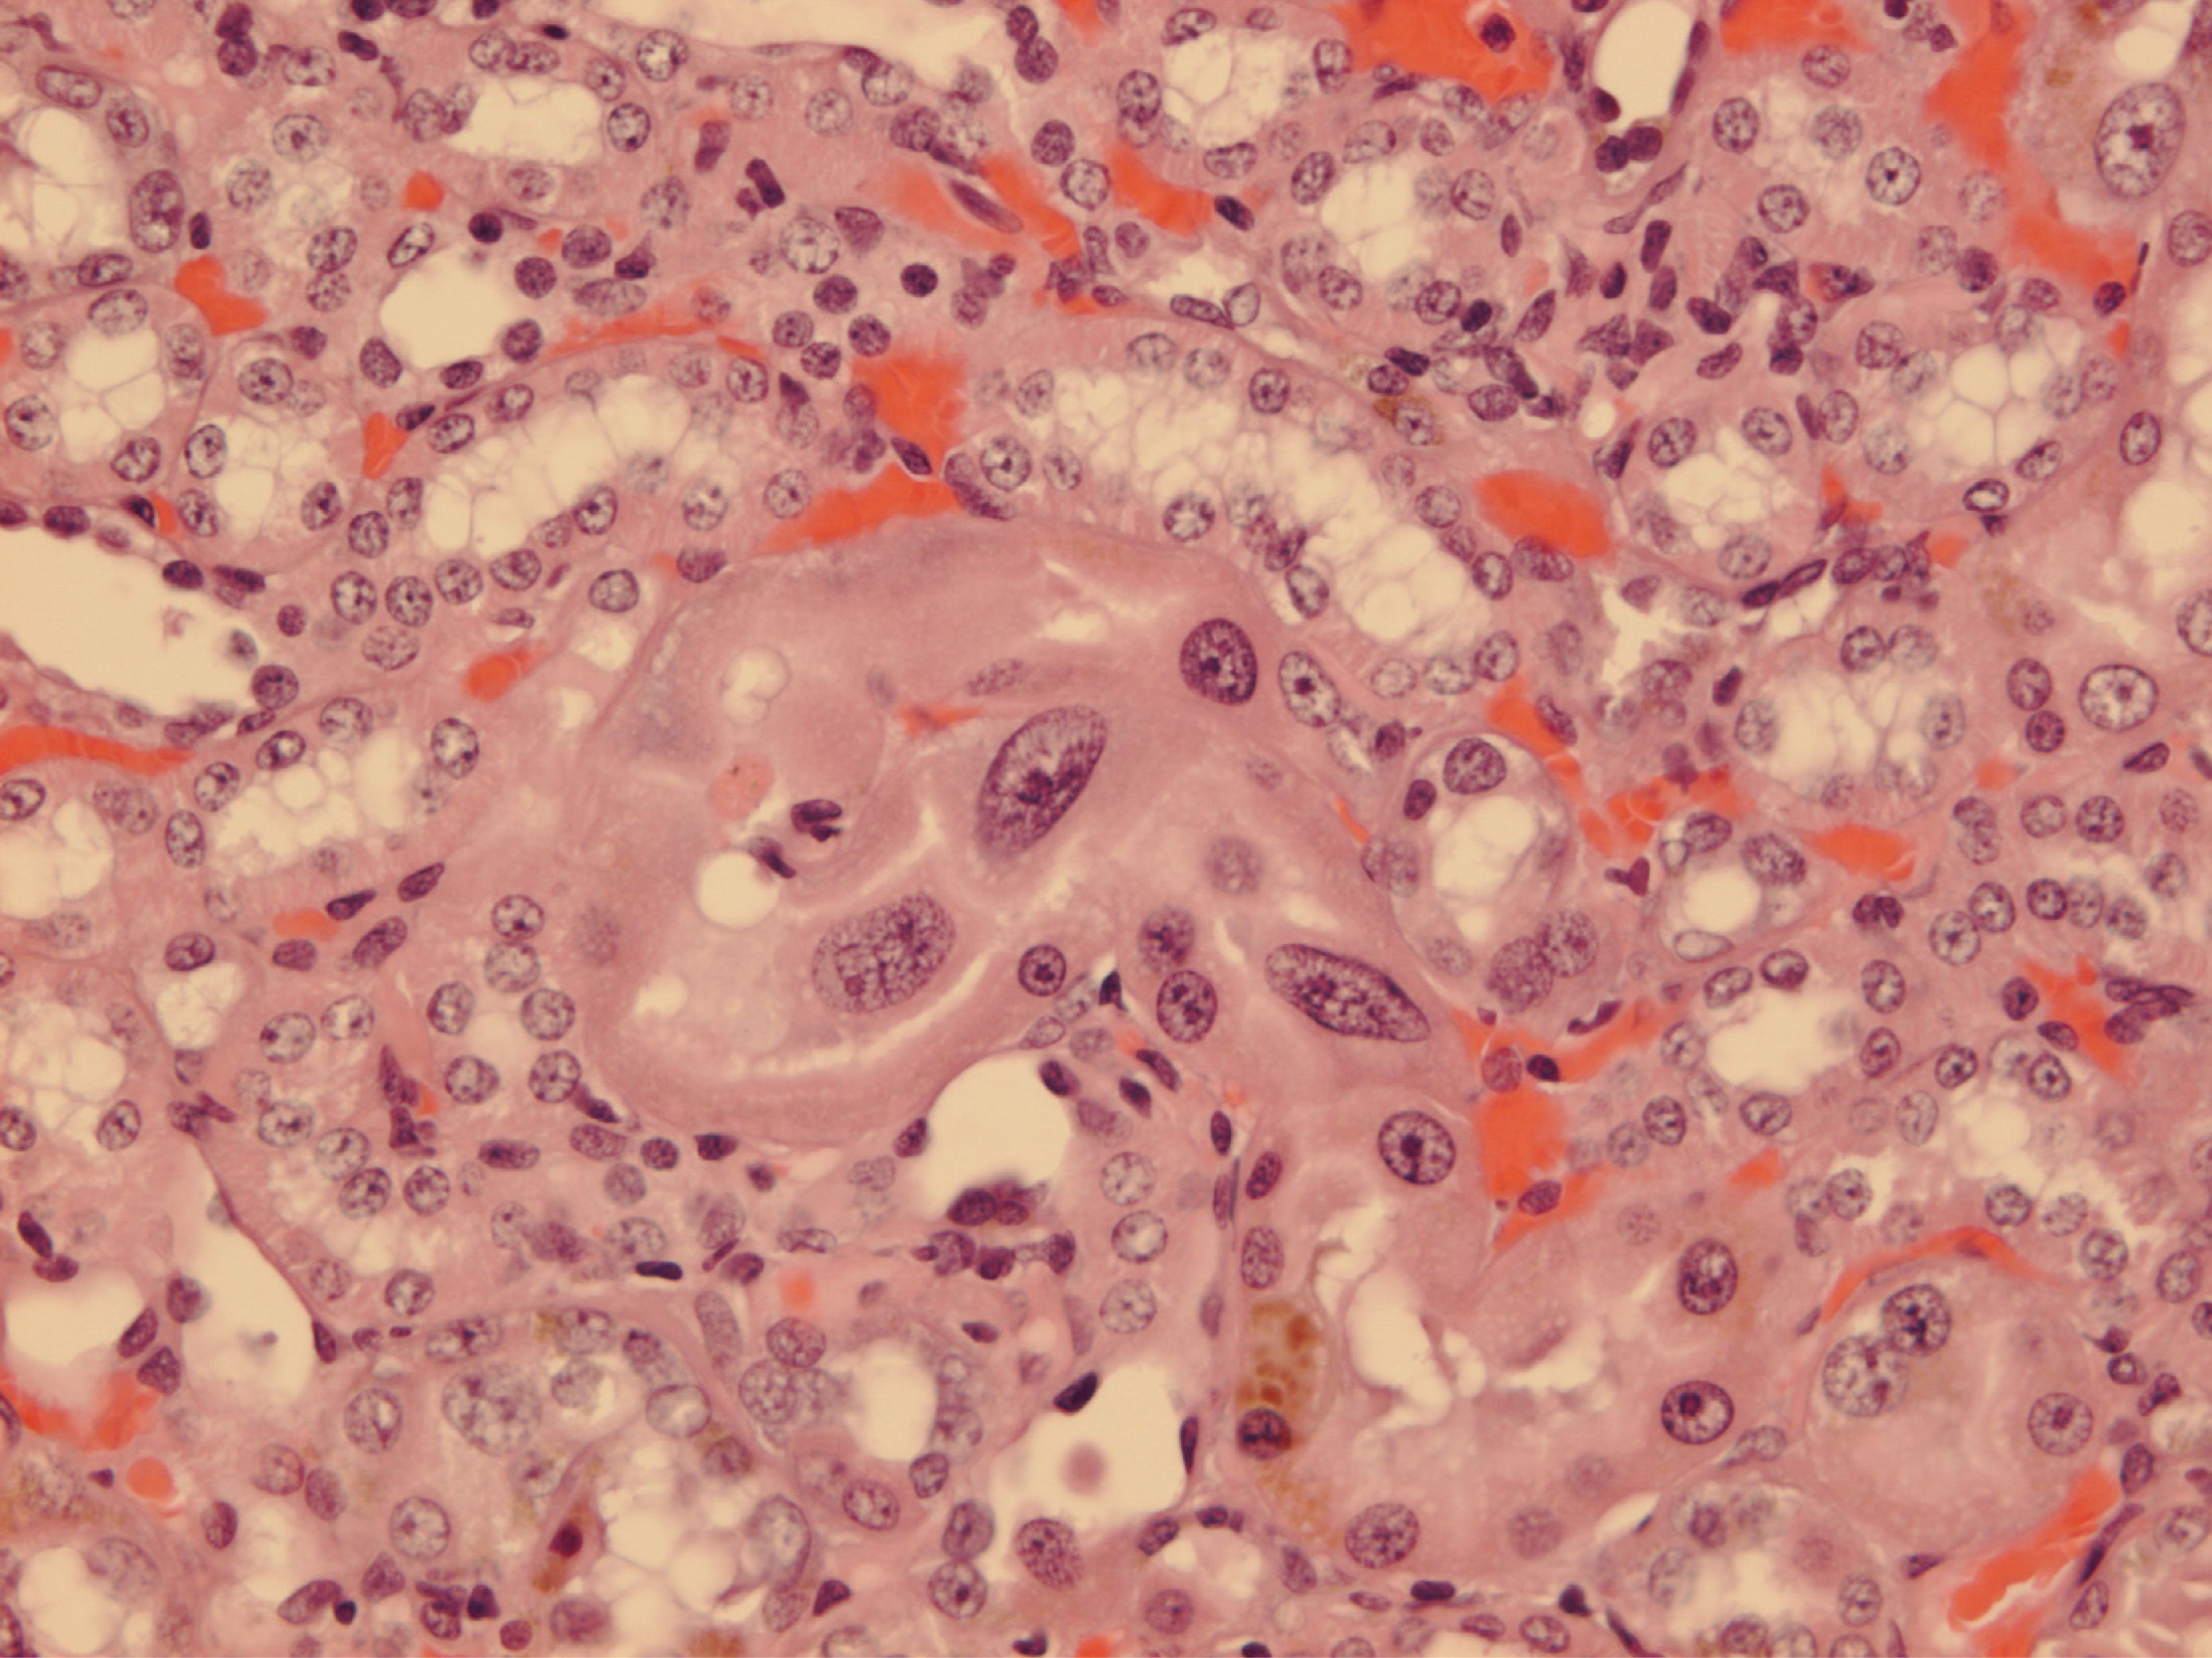

Courtesy of NTP Archives, we have been able to review H & E sections of the tumourous kidneys of Fischer females from the OTA study and study all the benign and malignant hyperplasias. Comparison with the more obvious tumours in male rats, reported in the NTP study and also illustrated from recent experiments [16, 17], can be made from the example shown in Figure 3AB. In contrast, Figure 3C shows the magnitude of the largest (4mm diameter) carcinoma in female rats of the NTP study, and which did not even distort the kidney. Nevertheless, detailed histopathology shown in Figure 4A, B illustrates that there was typical disorganised carcinoma with many enlarged nuclei with prominent nucleoli, infiltrating surrounding renal parenchyma and reminiscent of that of male rat renal carcinomas in which DNA ploidy distribution has been measured as consistently aneuploid [16]. A surprising observation was extensive kayomegaly focused within the renal papilla of all female rat tumour-bearing kidneys of the high OTA dose group, where the section passed though the papilla (Figure 4C). This does not seem to have been reported before, but in the present context is interpreted as consequential in the female of a smaller proportion of excreted OTA, being transported into proximal tubule epithelia than in the male. Some free OTA in glomerular filtrate may then have been available to affect epithelia in the loop of Henle. Since the carcinomas were all unilateral and microscopic, and were discovered only at the end of the study, they were most unlikely at that stage to have significantly affected health. Another, even smaller carcinoma is shown in Figure 4D. None of the three carcinomas had metastasised.

Figure 4. Micrographs of H & E sections of NTP female high OTA dose Fischer rats. A-C, detail of section in Figure 4C. A, representative carcinoma. B, carcinoma infiltrating renal medulla. C, prominent karyomegaly in the renal papilla. D, another example of a small renal carcinoma with necrotic centre, located at the corticomedullary junction.